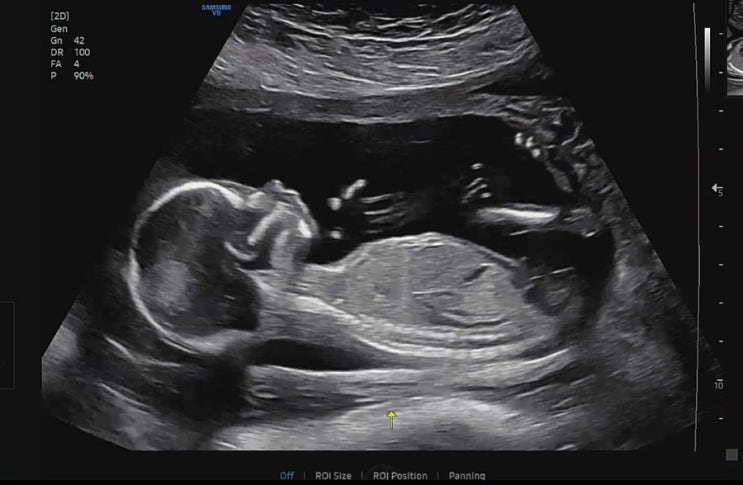

임신일기-23,24주 공포의 임당검사 재검 당첨

역류성 식도염이 너무 심해 도저히 안되겠다하고 영양제를 끊었다. 의사와 상담한 건 아니고 중학교때부터 ...